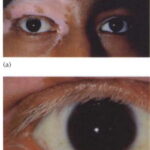

OCULAR DISEASE

Although patients with vitiligo do not usually have ophthalmologic complaints, they can have several ocular findings. Pigmentary abnormalities of the iris and retina may occur. Choroidal abnormalities have been reported in up to 30 percent of patients and iritis in approximately 5 percent. Uveitis can be a frequent ocular manifestation. Exophthalmos may occur in the setting of concomitant Graves disease. Visual acuity is generally not affected.

VOGT-KOYANAGI-HARADA SYNDROME

The Vogt-Koyanagi-Harada syndrome (VKH) consists of vitiligo in association with uveitis, aseptic meningitis, dysacusis, tinnitus, poliosis, and alopecia. It is a rare, systemic, T-cell-mediated autoimmune disorder. VKH syndrome is associated with other autoimmune disorders such as autoimmune polyglandular syndrome, hypothyroidism, Hashimoto thyroiditis, and diabetes mellitus. VKH syndrome classically occurs in three phases. During the first phase, the meningoencephalic phase, patients may have headache, meningismus, seizures, muscle weakness, or paralysis after a prodrome of fever, malaise, nausea and vomiting. Subsequently, the acute ophthalmic phase occurs when patients may develop photophobia, eye pain, and altered visual acuity. Patients may develop uveitis, iridocyclitis, choroiditis, and retinal detachment during this phase and can later develop complications such as cataracts and glaucoma. Vitiligo, alopecia, and poliosis22 usually follow, but can occur before the other manifestations.